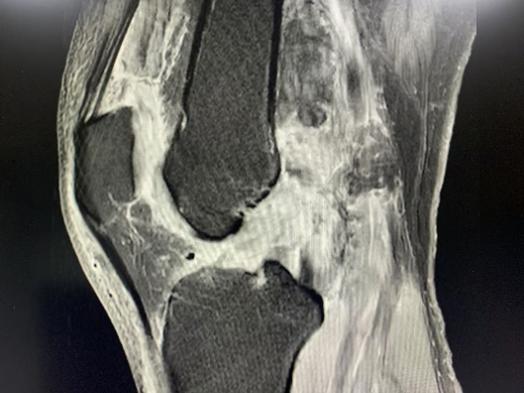

61岁的刘先生因交通事故,导致右膝关节支持带内侧支持带、内侧副韧带及前交叉韧带损伤;右膝内外侧半月板损伤II度;右股骨外侧髁挫伤。59岁的周先生因交通事故,导致左膝后交叉韧带断裂,内侧副韧带断裂。